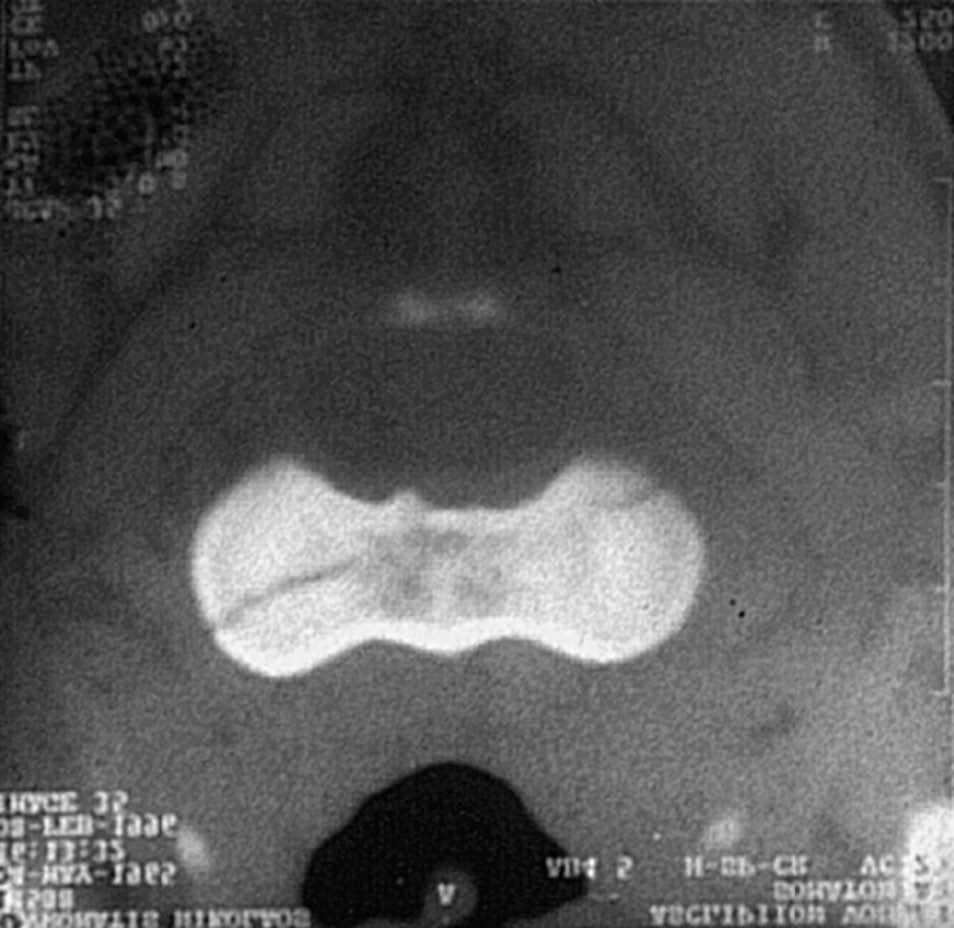

Estas lesiones son muy raras y suceden probablemente por la aplicación de fuerzas verticales y de flexión, mientras el arco posterior de C2 es inmovilizado con el de C3. Las radiografías convencionales no son útiles para el diagnóstico; la TAC es el método diagnóstico por excelencia, el más seguro (fig. 9). Estas lesiones son estables y tienen un buen pronóstico con tratamiento conservador mediante el uso de un collar de Philadelphia durante 8 o 10 semanas.

Figura 9. Imagen de tomografía axial computarizada (TAC) de fractura longitudinal.